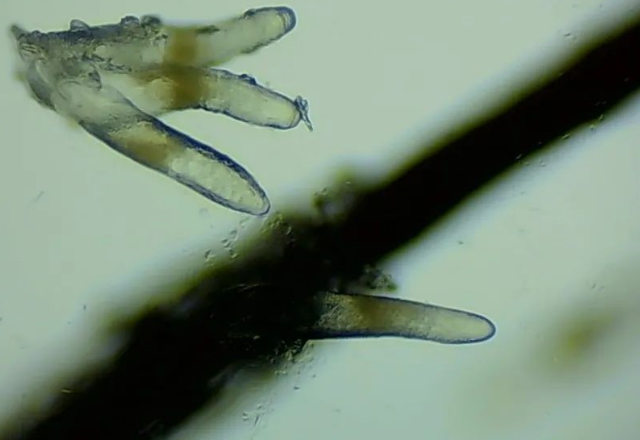

螨蟲檢查

▲顯微鏡下,睫毛上的螨蟲,它們長著透明膠狀的身體,揮舞著爪子。